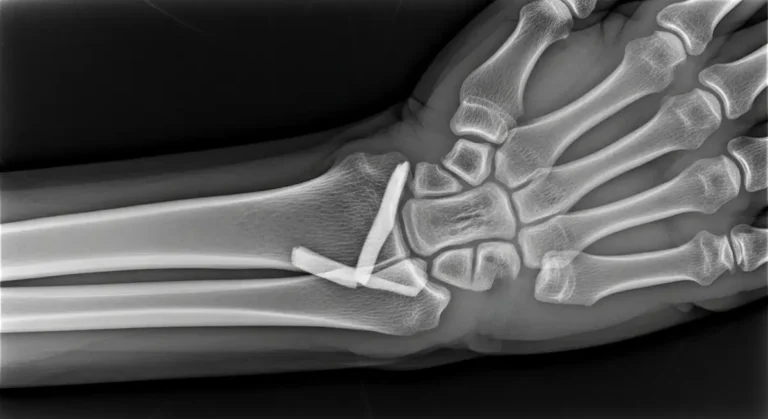

Já nos casos em que há desvio dos fragmentos, rotação dos dedos ou comprometimento da função da mão, é necessária intervenção cirúrgica.

Na cirurgia, são utilizadas técnicas como fixação com pinos, placas ou parafusos, sempre buscando restaurar a anatomia do osso e preservar ao máximo a mobilidade.